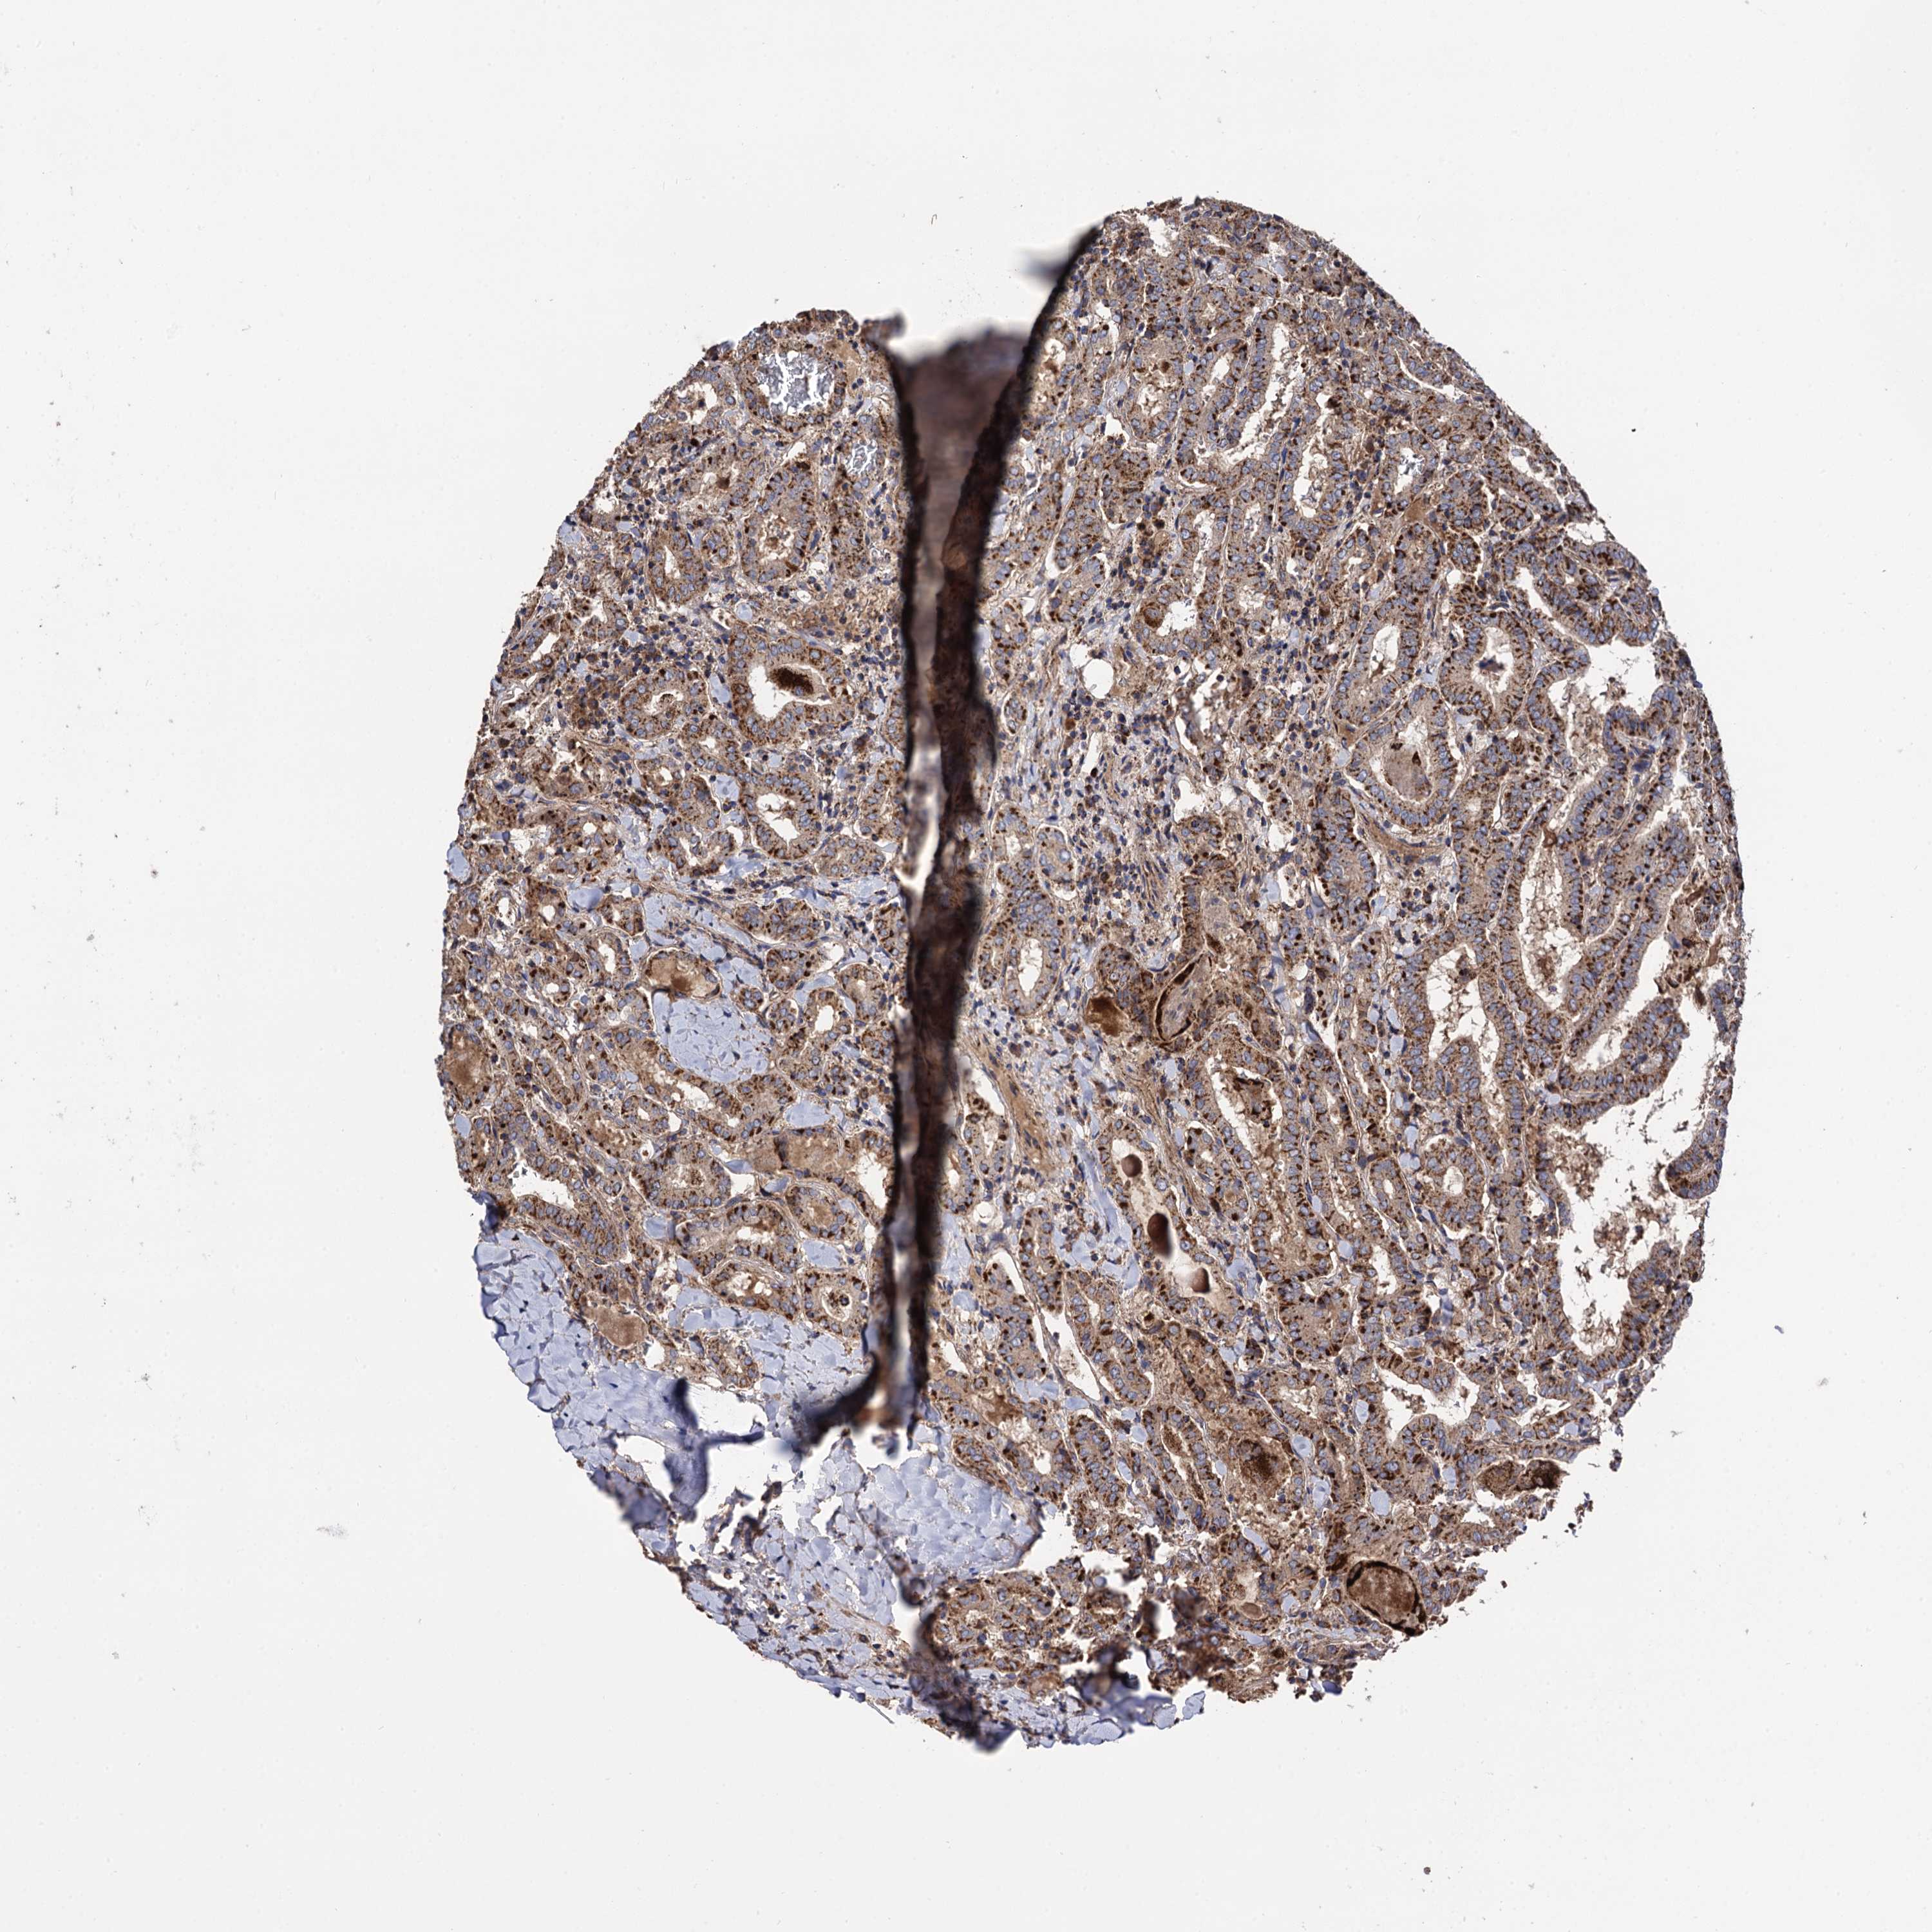

THYROID CANCER - Protein expressioni

A mouse-over function shows sample information and annotation data. Click on an image to view it in a full screen mode. Samples can be filtered based on level of antibody staining by selecting one or several of the following categories: high, medium, low and not detected. The assay and annotation is described here.

Note that samples used for immunohistochemistry by the Human Protein Atlas do not correspond to samples in the TCGA dataset.

Antibody stainingi

Antibody staining in the annotated cell types in the current human tissue is reported as not detected, low, medium, or high, based on conventional immunohistochemistry profiling in selected tissues. This score is based on the combination of the staining intensity and fraction of stained cells.

Each image is clickable and will lead to virtual microscopy that enables deeper exploration of all samples and also displays staining intensity scores, fraction scores and subcellular localization as well as patient and tissue information for each sample.

Antibody HPA040845

Staining

High

Medium

Low

Not detected

Intensity

Strong

Moderate

Weak

Negative

Quantity

>75%

75%-25%

<25%

None

Location

Nuclear

Cytoplasmic/membranous

Cytoplasmic/membranous,nuclear

Papillary adenocarcinoma, NOS

Follicular adenoma carcinoma, NOS